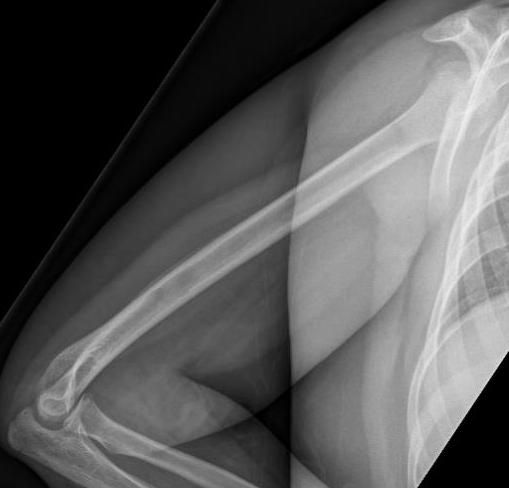

Subtle periosteal reaction humerus